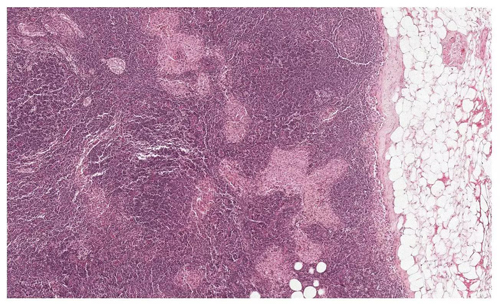

你能从这张切片中,找到哪些是肿瘤,哪些是正常组织,哪些是看起来很像肿瘤的正常组织吗?(图片来源:谷歌)

谷歌和Verily的科学家们做了一个尝试。由于单张切片的照片过于庞大,他们将这些图像分割成了数万至数十万个128x128像素的小区域,每个小区域内可能含有数个肿瘤细胞。随后,他们提供了许多肿瘤组织与正常组织的病理切片,供人工智能学习。最终,这款人工智能掌握了一项像素级的技巧——它能分辨出单个小区域内被标注为“肿瘤”的像素,从而将整个小区域标注为“肿瘤区”。这能有效将肿瘤组织与健康组织区分开来。

人工智能不但能找到肿瘤组织,还能区分看上去很接近的正常组织(图片来源:谷歌)